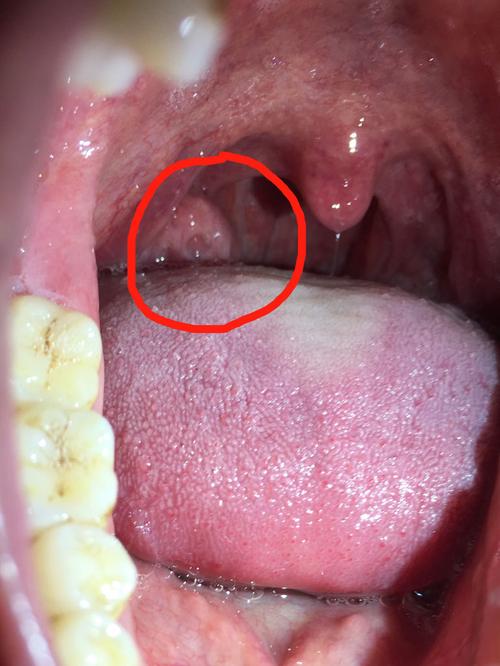

扁桃体肿大吃什么药

扁桃体肿大吃什么药,扁桃体肥大吃什么药

儿童扁桃体肿大图片

扁桃体肿大图解

扁桃体肿大

扁桃体肿大图片发炎

扁桃体肿大图片

扁桃体三度肿大图片

扁桃体二度肿大图片

扁桃体肿大图片对照

扁桃体肿大图片儿童

扁桃体肿大分度图片